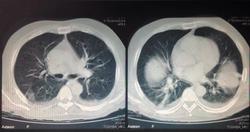

Пол пациента: Мужской пол Тип патологии: Злокачественное новообразование Область исследования: Грудная клетка и верхние дыхательные путиПищеварительная система Методы исследования: КТ к сожалению, ни анамнеза, ни жалоб у меня нет. только снимок. :( https://radiomed.ru/sites/default/files/styles/case_slider_image/public/user/19300/image_3_3.jpeg?itok=llGvHF8A https://radiomed.ru/sites/default/files/styles/case_slider_image/public/user/19300/image_1_3.jpeg?itok=m4fSrbr0 ID:33623 Пнд, 25/11/2013 - 16:58 #1 Петр Николаевич Не на сайте Был на сайте: 2 месяцев 2 недели назад Зарегистрирован: 15.03.2011 - 13:22 Публикации: 150 С чем разбираться? где снимки? Пнд, 25/11/2013 - 17:09 #2 Emchike Не на сайте Был на сайте: 10 лет 3 месяцев назад Зарегистрирован: 25.11.2013 - 14:06 Публикации: 4 анонимизированные изображенияПриложения: Пнд, 25/11/2013 - 17:12 #3 Helios Не на сайте Был на сайте: 1 год 2 недели назад Зарегистрирован: 06.08.2010 - 15:16 Публикации: 4417 Вот так-то лучше , но не совсем.Во-первых, жалобы, анамнез.Во-вторых, лучше дайкомы. Пнд, 25/11/2013 - 19:34 #4 Андрей Юрьевич Не на сайте Был на сайте: 2 недели 4 дня назад Зарегистрирован: 16.11.2008 - 22:16 Публикации: 18106 По тому, что видно - малый двусторонний гидроторакс. Андрей Юрьевич Пнд, 25/11/2013 - 19:50 #5 алкс Не на сайте Был на сайте: 10 лет 5 месяцев назад Зарегистрирован: 24.10.2012 - 22:55 Публикации: 2915 Андрей Юрьевич wrote: По тому, что видно - малый двусторонний гидроторакс. + Но это НЕ МРТ! Втр, 26/11/2013 - 00:38 #6 Emchike Не на сайте Был на сайте: 10 лет 3 месяцев назад Зарегистрирован: 25.11.2013 - 14:06 Публикации: 4 спасибо Втр, 26/11/2013 - 01:54 #7 Thirteenth Не на сайте Был на сайте: 11 лет 10 месяцев назад Зарегистрирован: 26.11.2013 - 01:51 Публикации: 3 Сдается мне, что в брюшной полости свободный возхдух - перфорация полого органа?

По тому, что видно - малый двусторонний гидроторакс.